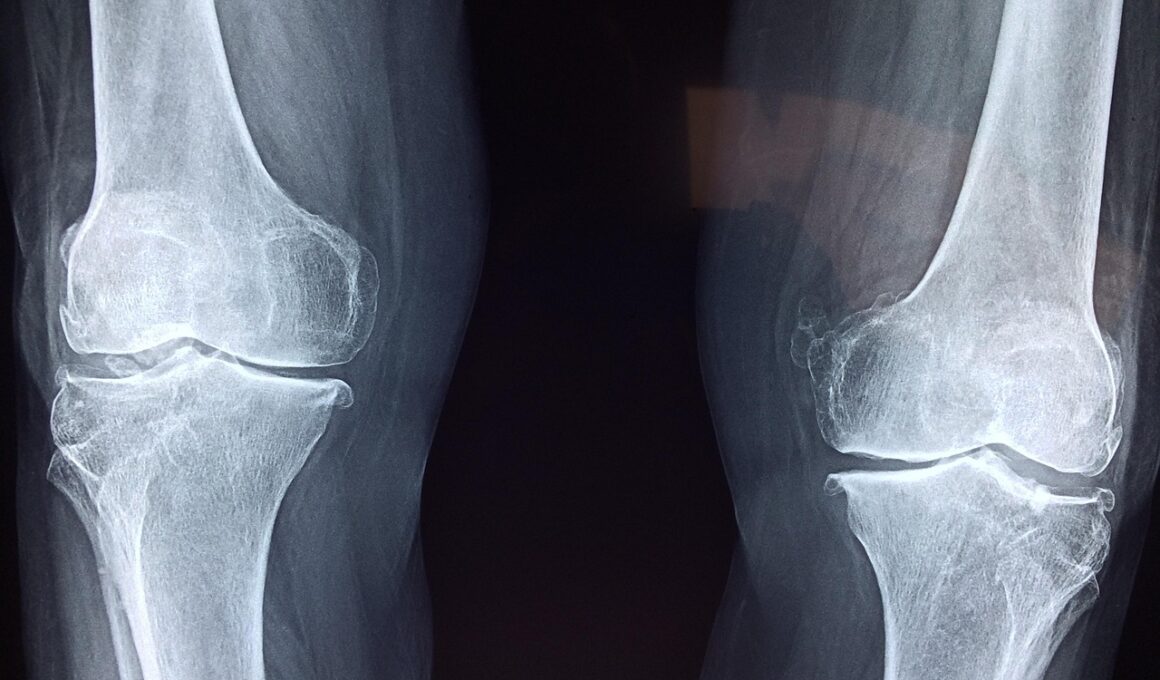

Aging is a natural process that can impact men’s bone health significantly. As men age, their bodies produce less testosterone, which can lead to decreased bone density. Usually, men are at risk of osteoporosis, often misperceived as a women’s issue. Hence, awareness of osteoporotic signs, such as frequent fractures, should be prioritized. To counteract these changes, men should incorporate resistance training and stimulate testosterone production naturally via physical activity. Regular weight-bearing exercises help maintain bone strength. Furthermore, ensuring an intake of adequate protein is essential; protein plays a crucial role in bone health by aiding in the formation and maintenance of bone tissue, which is vital as one ages. Regular medical screenings can assist in monitoring bone health and assist in outlining specific dietary and lifestyle changes necessary for improved bone density. Men should consult their healthcare provider on effective supplementation, particularly vitamin D, to maximize calcium absorption. Moreover, understanding individual health history and family backgrounds is essential. Strategies like adopting a bone-healthy lifestyle will actively improve men’s bone health and facilitate independence into older adulthood.